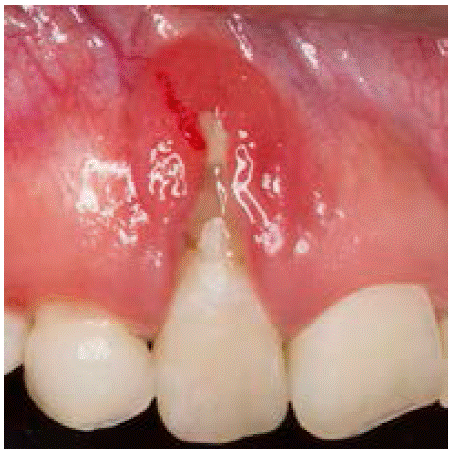

Una vez concluido el tratamiento endodóntico se programó la cirugía periodontal para ganar encía insertada y se decidió aplicar la técnica de doble papila; sin embargo, hubo poca ganancia de encía insertada, por lo mismo se decidió colocar un injerto gingival libre.

Antes de iniciar el procedimiento quirúrgico (injerto gingival libre), la paciente realizó colutorios con gluconato de clorhexidina al 0.12%, enseguida se aplicó la técnica de anestesia supraperióstica en el diente 12 y así posteriormente preparar el sitio receptor, el sitio donador fue la zona palatina, se obtuvo un injerto de alrededor de 1mm de espesor y se suturó con puntos simples aislados con ácido poliglicólico 5-0. Ambas heridas se protegieron con un apósito periodontal.

Dos meses después se efectuó la cirugía periodontal para ganar altura y espesor gingival, se realizó un desplazado coronal más injerto de tejido conectivo subepitelial (ITCS) (Figura 3A).

Figura 3: A) Preparación del lecho receptor (ITCS). B) Adaptación del injerto de tejido conectivo subepitelial. C) Cicatrización a los 15 días después de haber realizado la cobertura radicular. D) Revisión clínica cuatro meses después del procedimiento de cobertura radicular.

El ITCS fue tomado de la zona palatina, se removió el tejido adiposo y el epitelio subyacente (Figura 3B). Este injerto se colocó en el sitio receptor suturándolo a las papilas interdentales con puntos suspensorios coronales, posteriormente se realizó el desplazado coronal del colgajo combinando puntos simples aislados con suspensorios coronales, para esto se usó sutura de ácido poliglicólico 5-0.

A los 15 días se retiró el apósito periodontal y la sutura se retiró a las dos semanas después del procedimiento. La paciente no tuvo complicaciones posto peratorias (Figura 3C).

Se hicieron revisiones periodontales periódicas, cuatro meses después de la segunda cirugía se observó que la cobertura radicular era de 90% aproximadamente en el diente 12, por lo mismo se decidió efectuar la cobertura radicular con la técnica semilunar, siendo una técnica indicada para recesiones pequeñas y con buena cantidad de encía insertada (Figura 3D).